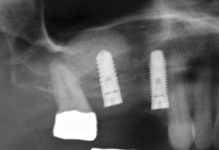

Při ztrátě molárů a premolárů v horní čelisti a jejich náhradě implantáty se často setkáváme s nedostatečnou

vertikální nabídkou kosti pod čelistní dutinou, často doprovázenou i nedostatečnou horizontální nabídkou a sníženou kvalitou kosti (v oblasti 2. premoláru v 50%, v oblasti moláru až v 80% případů nedostatečná kostní nabídka)

Od roku 1985 je tento problém řešen augmentační operací nazývanou

sinus lift.

Jedná se o vyzvednutí membrány, která čelistní dutinu vystýlá, pod vyzvednutou membránou vznikne kapsa, kam se umístí augmentační materiál, do kterého se zavedou implantáty.